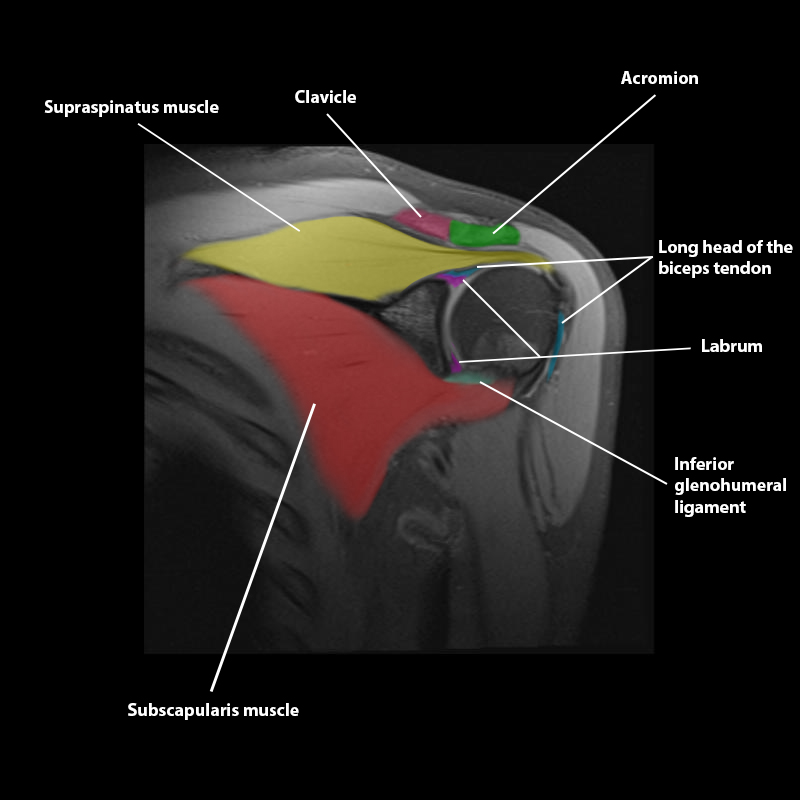

Shoulder MRI Anatomy